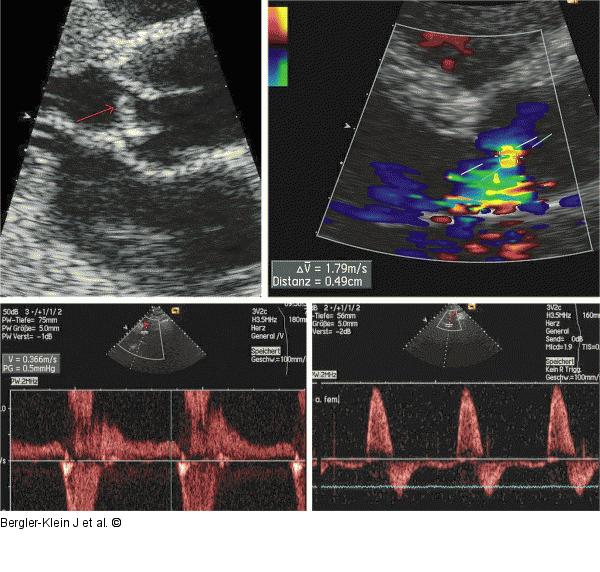

Abbildung 5: Aorteninsuffizienz Beispiele für die echokardiographische Untersuchung bei Aorteninsuffizienz: Prolaps des akoronaren Segels, Messung der Vena contracta des – in diesem Fall exzentrischen – Aorteninsuffizienzjets. Diastolische Flussumkehr in der Aorta descendens mit enddiastolischer Geschwindigkeit 0,33 m/sec. Holodiastolischer Reflux in der Arteria iliaca. |

Beispiele für die echokardiographische Untersuchung bei Aorteninsuffizienz: Prolaps des akoronaren Segels, Messung der Vena contracta des – in diesem Fall exzentrischen – Aorteninsuffizienzjets. Diastolische Flussumkehr in der Aorta descendens mit enddiastolischer Geschwindigkeit 0,33 m/sec. Holodiastolischer Reflux in der Arteria iliaca. |